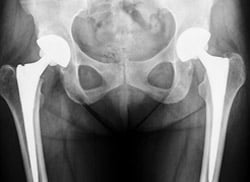

Case #66: Bilateral total hip replacement